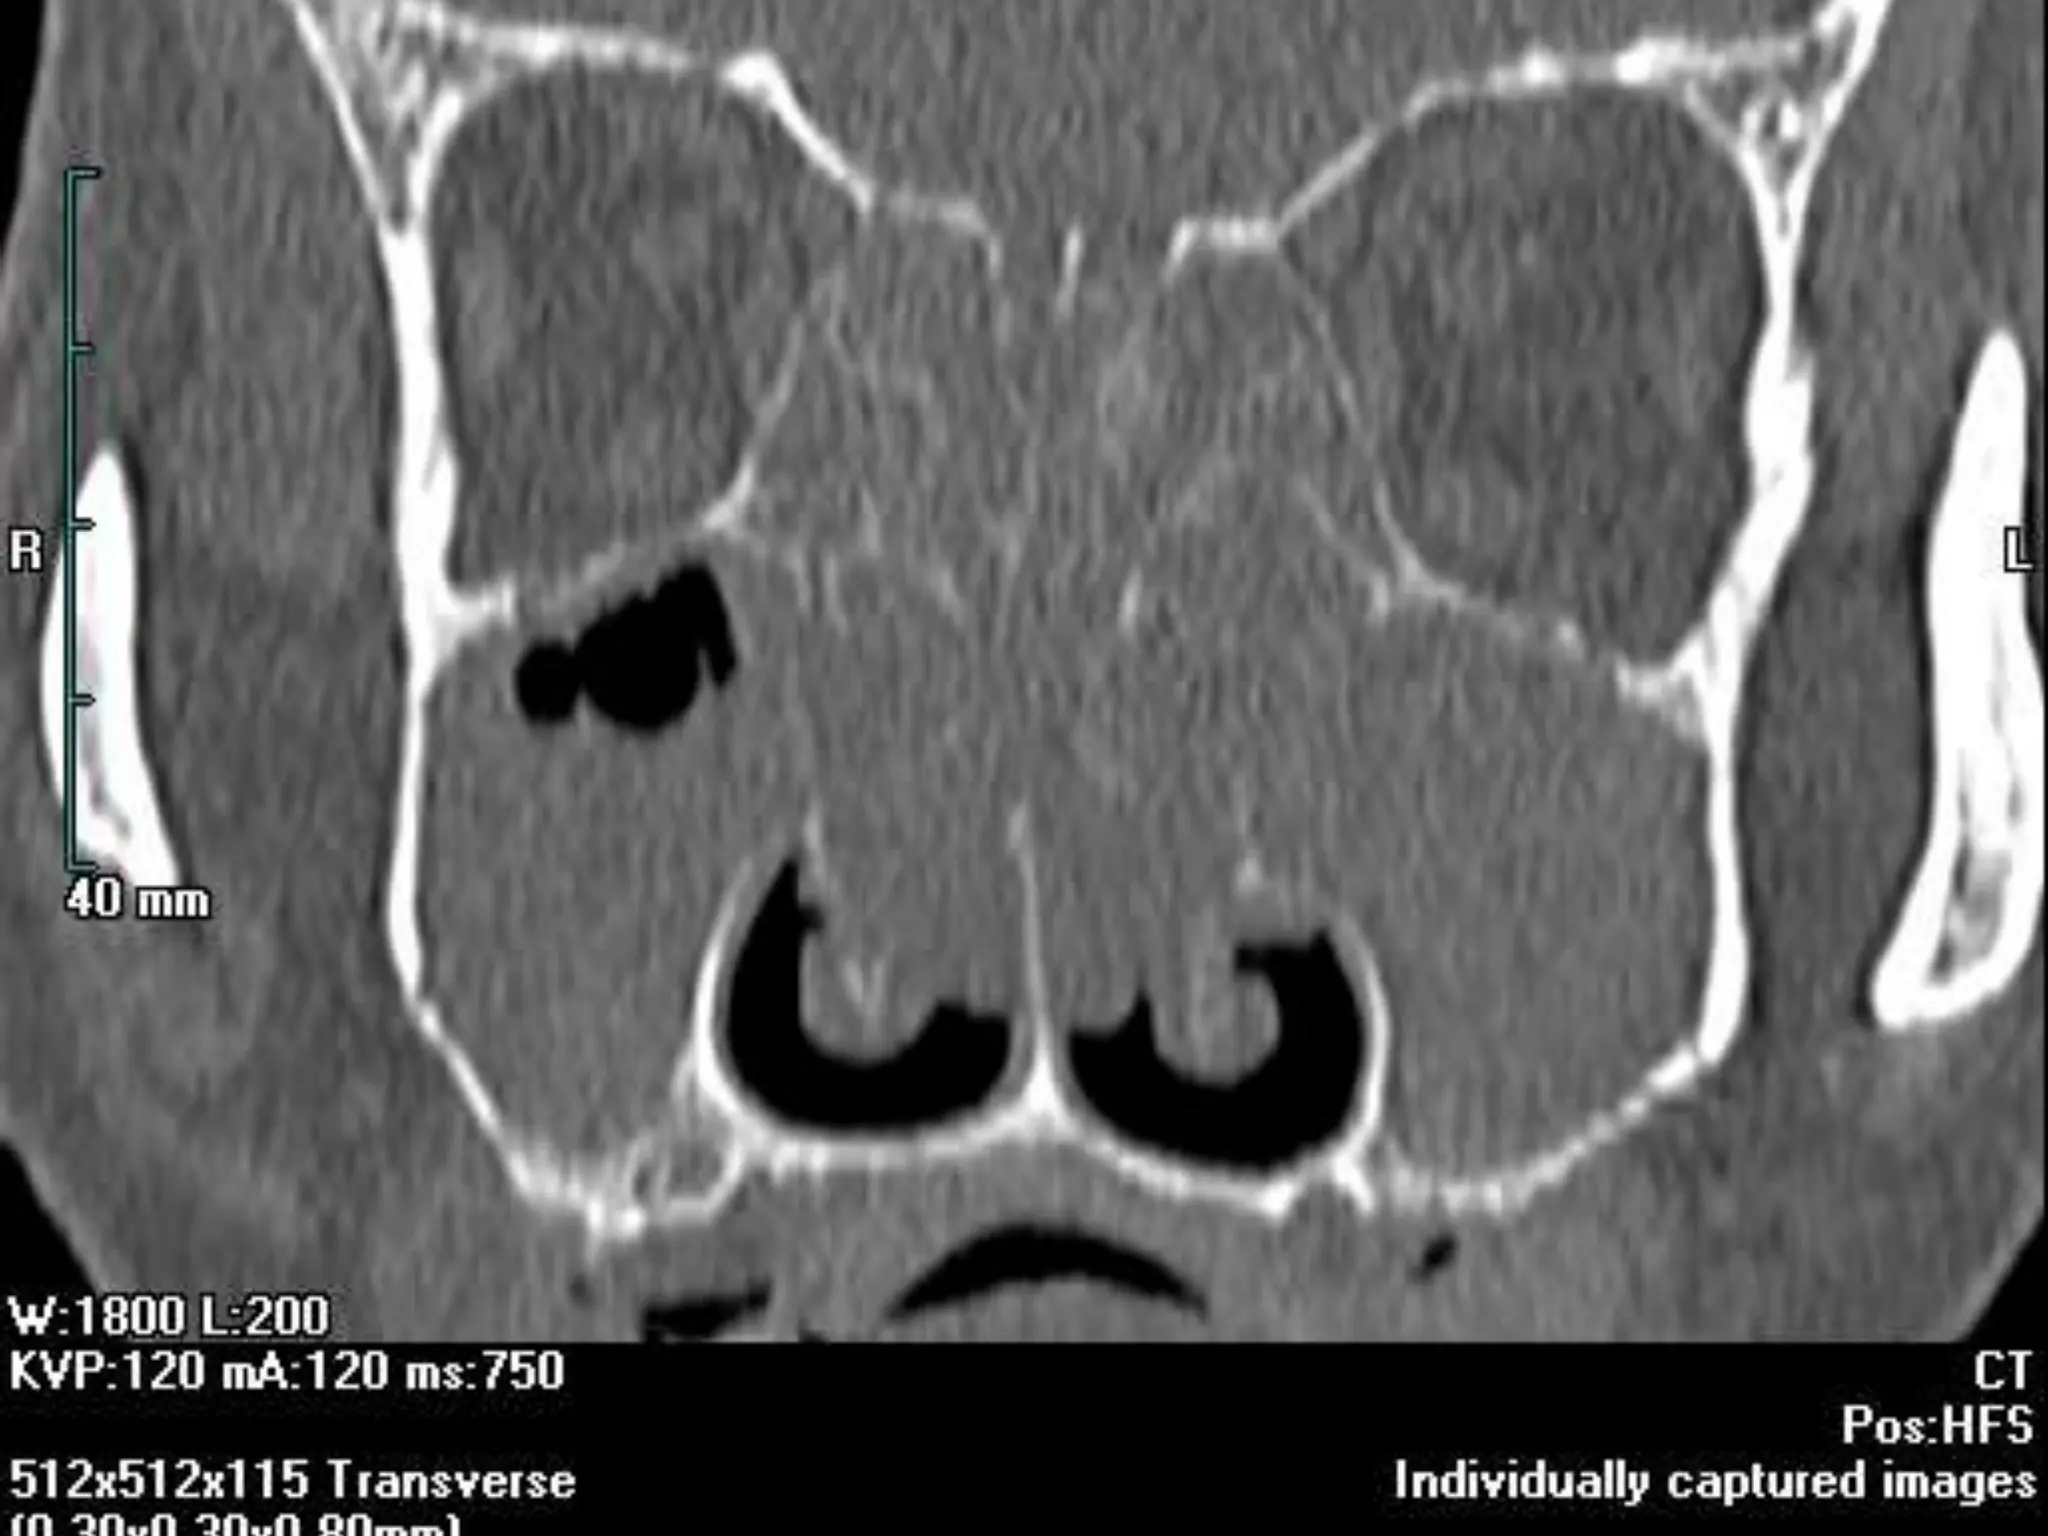

CORONAL ANATOMY

• #8 Figure 1 (A, B): (A) Coronal CT scan shows the osteomeatal complex which comprises of - infundibulum (dotted line), hiatus semilunaris (asterisk), maxillary ostium (arrow) and Ethmoidal bulla (EB). MT-middle turbinate, LP-lamina papyracea. (B) Coronal CT images reveals a prominent agger nasi cell (A) inferior and lateral to the nasofrontal recess (solid curved line). The medial relationship of the recess is formed by the middle turbinate (MT)